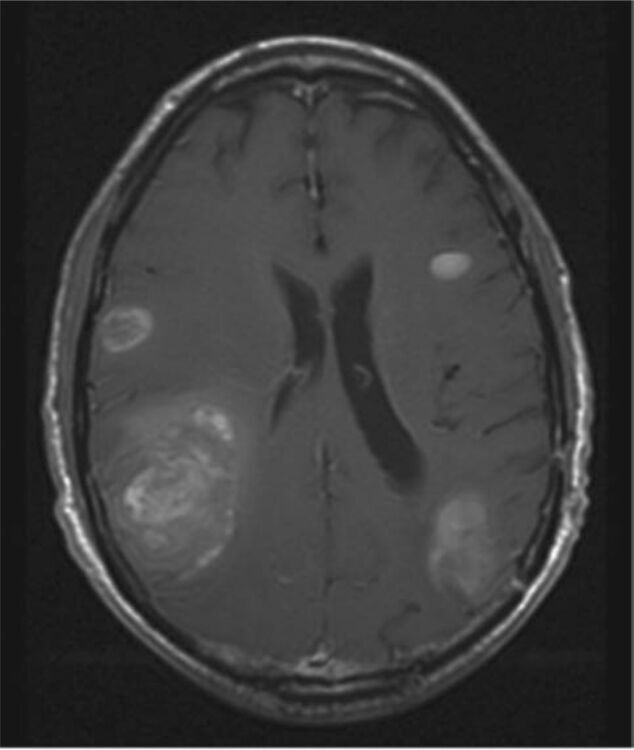

Join us every Thursday at 8 AM for a unique and informative Zoom event where medical experts gather to conduct a Brain Metastasis Tumor Board. During this virtual gathering, doctors will meticulously review complex patient cases, sharing their insights and knowledge on the latest advancements in brain metastasis treatment.

This interactive event is a valuable opportunity to witness the collaboration of top multi-disciplinary medical professionals as they discuss challenging cases and explore innovative solutions. To participate, registration for the event is required. Don't miss out on this weekly insight into the world of brain metastasis treatment and research!